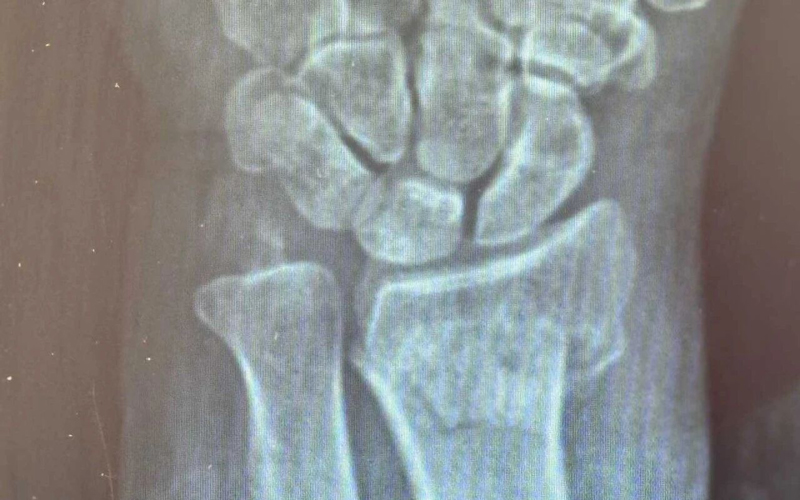

洗菜摔伤治疗前后对比

厕所摔伤治疗前后对比